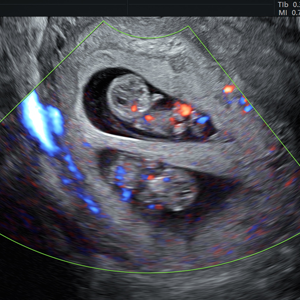

- Pionero en México en ofrecer diagnóstico por ultrasonido dentro del consultorio, así como en incorporar tecnología 3D y Doppler.